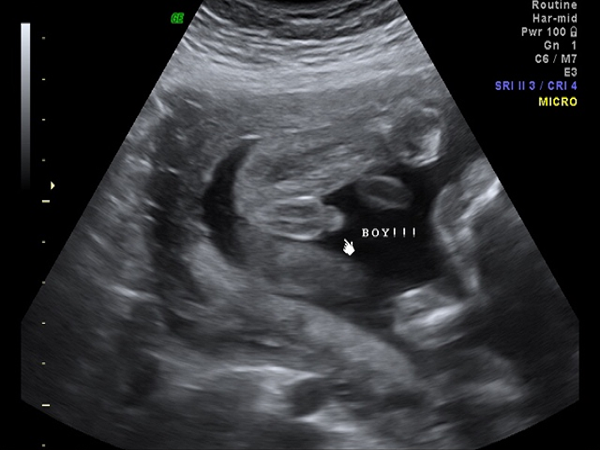

众所周知,胎儿的性别需要通过B超检查才能够准确判断,但是由于我国禁止非医学需要的性别鉴定,因此在怀孕21周的时候做B超检查医生是不会告诉家长孩子的性别的。但其实这个时候胎儿的生殖器官已经基本形成,所以家长们是可以自己通过B超中胎儿腿部间的特点来判断男女的,一般认为孩子的腿间有凸起来的亮点的就是男孩,如果双腿之间有白线的,那么就是女孩。

1看亮点:如果在B超检查图上看到胎儿的两腿之间平平的没有亮点的话,那么就说明怀的是女孩,反之,所以B超结果图上胎儿腿部间有凸起的尖尖的一个亮点的话,那就是男孩的生殖器官,说明怀的是男宝;2看白线:如果在B超检查图上看到宝宝的腿间有三条白线,这一般就是女宝宝的***,说明怀的是个女孩。如果B超单上没有白线,腿部之后圆圆的一坨的话,那就说明怀的是男孩。

总而言之,通过B超单上孩子腿部间的白线和亮点就能够准确判断出胎儿的性别。除此之外,还能够通过B超数据来进行判断,一般认为孕囊长和宽相差一倍以上的就是男孩,相差不大的就是生女孩。当然这些方法的准确率也不是百分之百的,所以大家一定要理性看待。